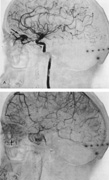

Of particular interest are those AVMs that involve the occipital lobe (Fig. 9). The clinical differentiation of migraine from a cerebral AVM was previously regarded as difficult because the clinical features of occipital lobe AVMs include visual phenomena or headaches. However, in most cases the clinical distinction is possible. In 26 cases with occipital AVM, two distinct syndromes were defined in 18 patients: occipital epilepsy and occipital apoplexy.73 Focal seizures with occipital malformations consist of elementary visual sensations similar to the phenomena evoked by direct cortical stimulations. When seizure activity occurs in the striate cortex (area 17), the patient usually reports sensations of moving lights in the right or left homonymous fields. The sensations are poorly formed, episodic, usually brief, sometimes colored, and unassociated with the angular, scintillating figures so characteristic of migrainous cortical phenomena. Epileptic discharges from areas 18 and 19 cause photopsias that are unlikely to remain stationary and to flicker rapidly. The epileptic photopsias usually last only seconds; occasionally they last for a few minutes before the onset of a generalized seizure. In other instances only the brief visual episodes occur without spreading to produce a generalized seizure. Momentary dimming or blindness in one or both homonymous fields may be experienced with seizure activity in the occipital areas.

Fig. 9. Carotid arteriogram of an occipital lobe arteriovenous malformation (AVM). Lateral (A) and frontal (B) projections demonstrating a small occipital AVM (arrow). The patient was a 23-year-old woman who presented with severe apoplectic unilateral headache, total left homonymous hemianopia, and mild nuchal rigidity. Despite xanthochromic cerebrospinal fluid, she was initially diagnosed elsewhere as having migraine. An AVM was successfully resected, and a small occipital lobe hematoma was removed.